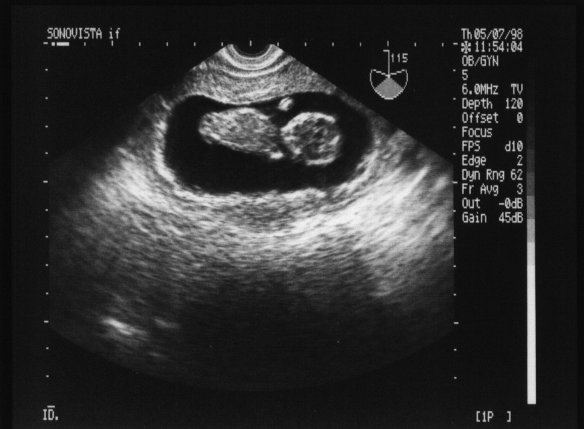

98年5月7日(妊娠11週3日)

この写真を初めて見たときは,とても感動した. 体長は約5cm. シロウト目に見ても,小さい手が写ってるのが分る!! なんと可愛い.^o^